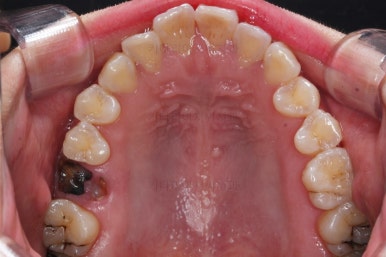

1. 초진

초진 시 입안의 모습입니다.

윗니-아랫니를 각각 보면 치아가 썩고 부러져 뿌리만 남은 치아가 많이 보입니다.

남은 치아들도 곳곳에 충치가 보이고요.